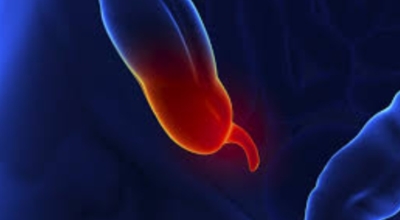

맹장염은 맹장 끝 충수돌기에 발생하는 염증이라고 볼 수 있으며, 보통 맹장염으로 알려져 있기는 하나 실질적으로는 부위가 충수돌기이기 때문에 의학 용어로는 충수염이라 하는 단어가 더욱 정확하다고 합니다. 맹장염(충수염)은 한국 사람들이 수술을 진행하는 질병 5위라고 불릴 정도로 자주 발생하며 매해 약 10만 명 정도가 수술을 받을 정도로 통상적으로 발생하는 질환입니다.

복통과 소화불량으로부터 시작하는 맹장염 초기 증상이 나타나는데 많은 분들이 소화기 계통 질환으로 오인해 약만 먹고 그냥 지나치는 경우가 많아요. 대장이 시작되는 부위를 맹장이라고 하며 그 끝부분에 약 5~10cm 정도의 길이로 꼬리처럼 달린 구조물을 충수 또는 충수돌기라고 하지만, 대개 말하는 맹장염은 이 충수가 막히거나 눌려서 염증이 발생해 통증이 생겨나게 되는데 심할 경우 터지는 경우가 발생하기도 합니다.